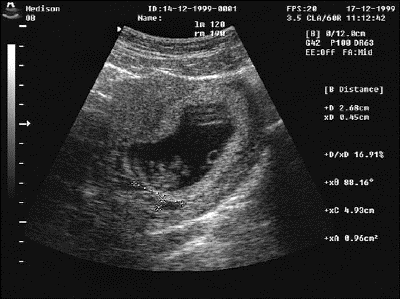

Для подтверждения замершей беременности осуществляется объективный осмотр пациентки. Удается установить отсутствие увеличения матки. Также больной назначается анализ крови на содержание гормона ХГЧ. При замирании беременности его уровень снижается и не соответствует показателям, которые свойственны для данного срока эмбриогенеза. Инструментальная диагностика заключается в проведении ультразвукового сканирования маточной полости. При замершей беременности отсутствуют любые признаки жизнедеятельности плода (двигательная активность, биение сердца).